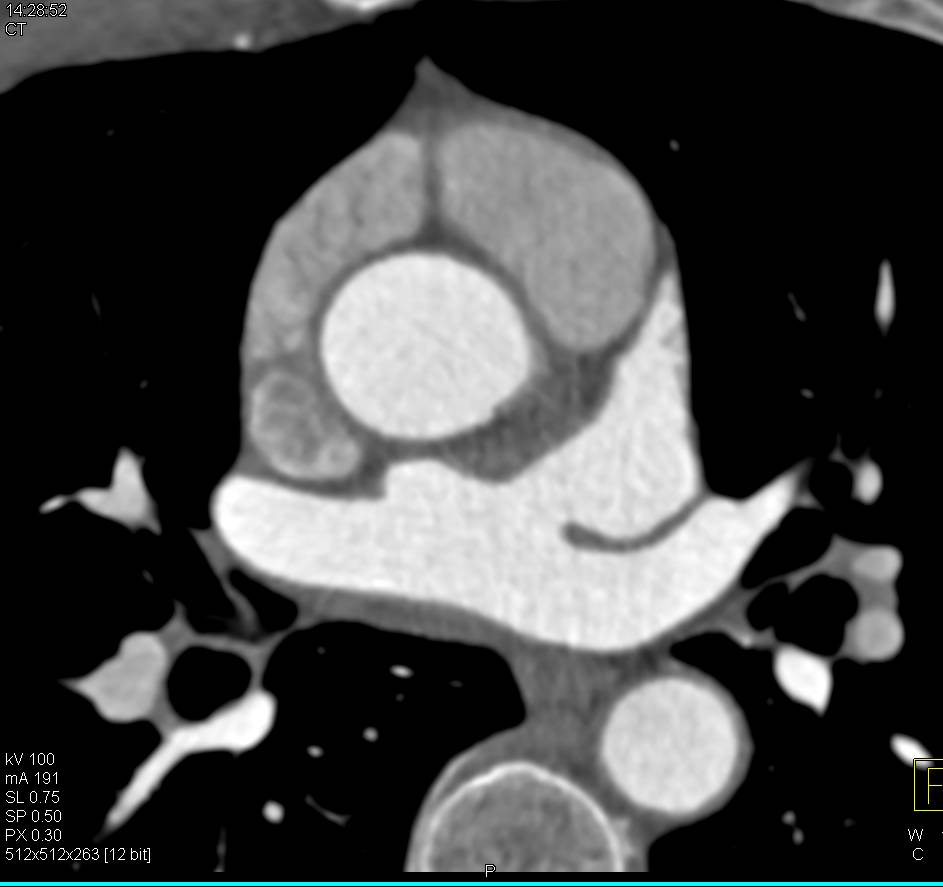

Run-off Study with Peripheral Vascular Disease